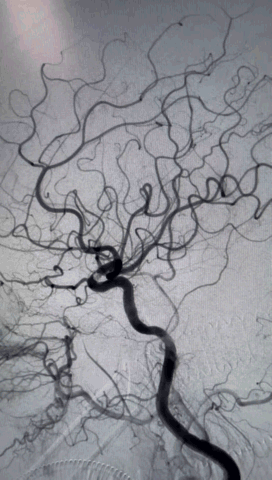

术前影像学检查结果

右侧股动脉穿刺,置8F鞘管,泥鳅导丝携6F 90cm Locaste输送导管内衬125cm多功能单弯导管超选至左侧颈内动脉C1段,6F 115cm Skathi远端通路导管到达C4段。

依据动脉瘤3D,调整机架位置使得动脉瘤及载瘤动脉显影最佳,Echelon-10微导管塑形理想,顺利超选至瘤内,先尝试单纯弹簧圈栓塞,必要时再采用支架辅助。

按大小顺序依次填塞弹簧圈(Jasper SS 3*8 Axium Prine 2*4、1*3)且弹簧圈成篮稳定,最终达到致密栓塞效果,手术过程顺利。

最终正侧位造影见载瘤动脉通畅,动脉瘤完全不显影,远端血管显影良好。